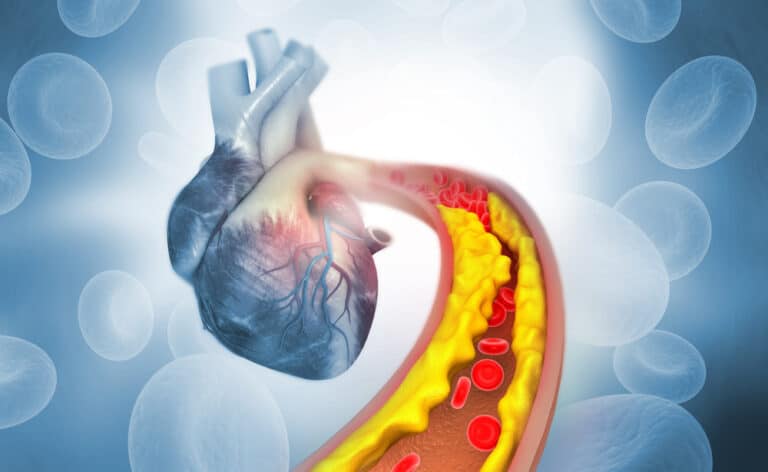

غير فيروس كورونا علامات صحة القلب في معظم المرضى، وأظهرت اختبارات التصوير القلبي دليلاً على الإصابة، كما أظهر مخطط صدى القلب عادة ضعف البطين الأيسر الانقباضي مع زيادة حجم القلب.

يذكر أن التهاب عضلة القلب أصبح من المضاعفات الأكثر انتشاراً في مرض فيروس كورونا، ونُشرت المزيد من الدراسات، نظراً لخطر التدهور المفاجئ لحالات المرضى، لذا إن معرفة هذه المضاعفات القلبية لمرضى فيروس كورونا أمر بالغ الأهمية لأخصائيي الرعاية الصحية،